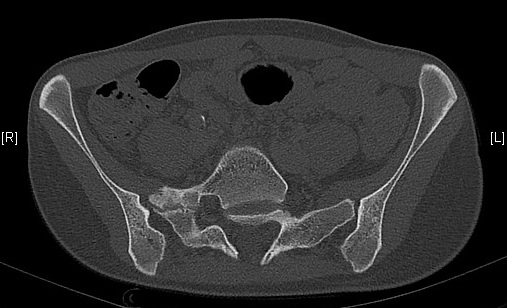

Scanner

Spina bifida occulta